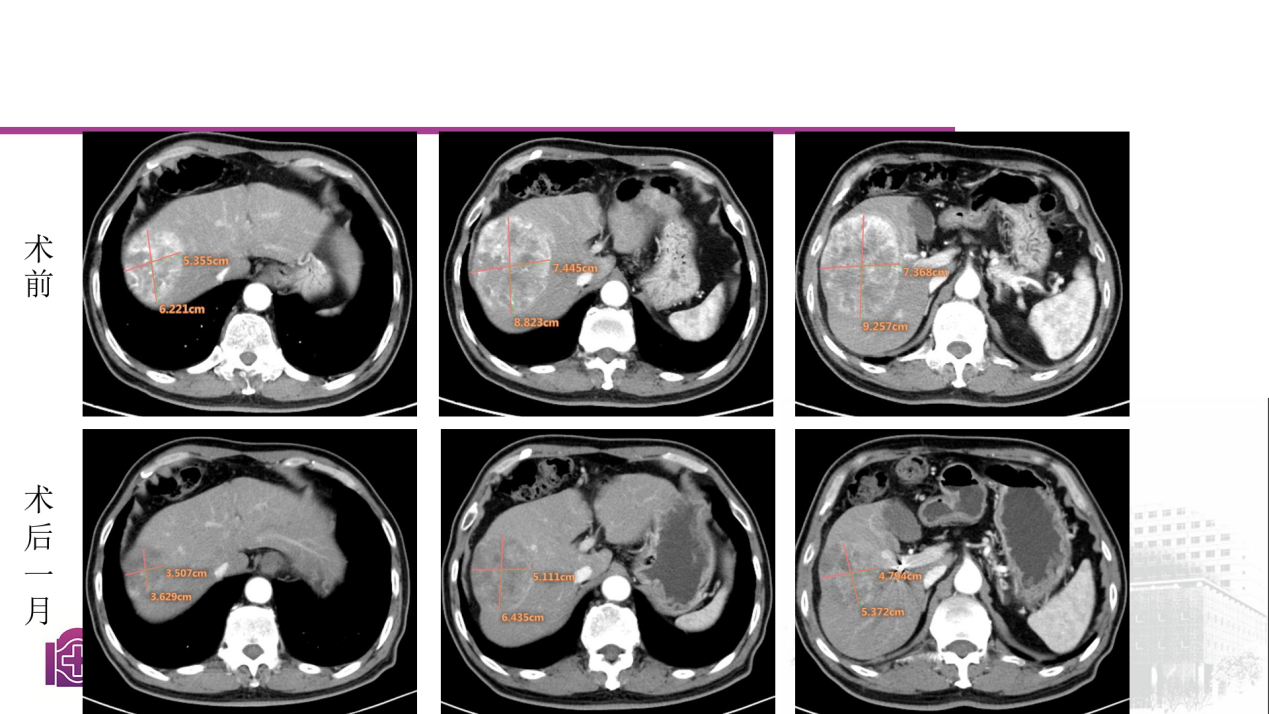

病例二:

60岁男性患者,诊断为HCC,肿瘤位于S5、S6、S7、S8段交汇处,既往接受靶向联合免疫等综合治疗,经综合评估后,行钇90树脂微球治疗,术中对肿瘤血管进行了优化处理策略,术后钇90微球分布良好,1个月复查,患者肿瘤体积缩小超过50%